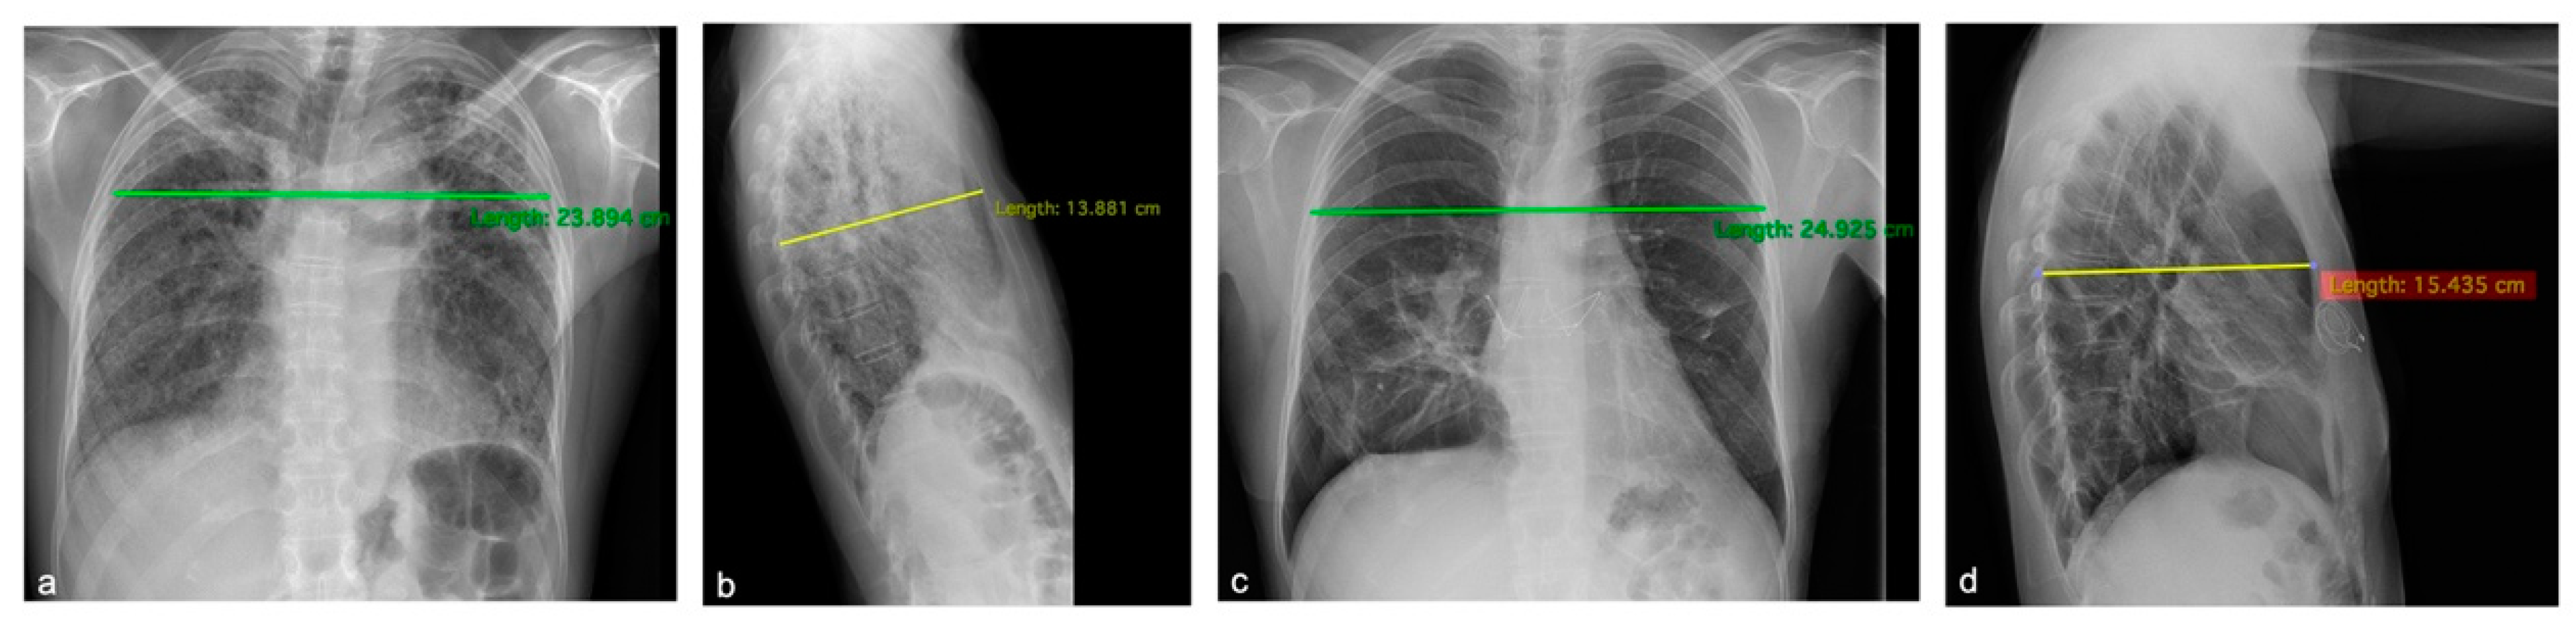

3.1.1. Patient 1

3.1.2. Patient 2